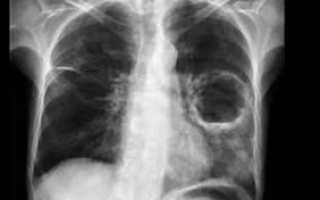

Абсцесс – еще одно гнойное заболевание легких. Это полость, окруженная капсулой из грануляций, фибрина и соединительной ткани. А внутри находятся экссудат и расплавленная ткань в виде гноя. Вокруг очага имеется реактивная инфильтрация или обусловленная предшествующей пневмонией.

- сделать рентген грудной клетки;

После попадания возбудителя в воздухоносные пути может начаться процесс воспаления ткани и отмирания клеток на определенных участках органа (абсцесс легких).

- Период формирования =напрямую зависит от причины и иммунитета организма. В среднем он продолжается от 3 дней до 3 недель.

- Следующий этап – вскрытие полости с гноем и отток мокроты через бронхи.